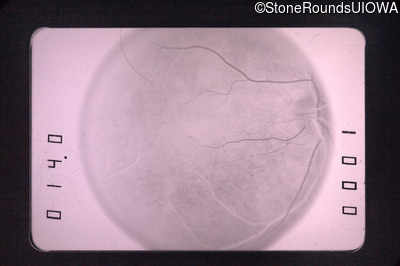

Fluorescein Angiography - Right - 20/50 +1

Exemplar